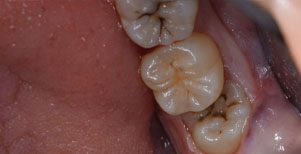

口腔内

半埋伏の親知らずでした。3糸縫合しました。